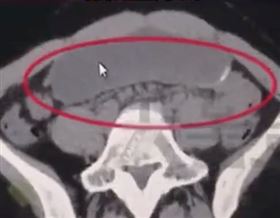

大胃王狂進食後 胃部X光照嚇歪網友

日本大胃女王萌梓(もえのあずき)身高156公分、體重...